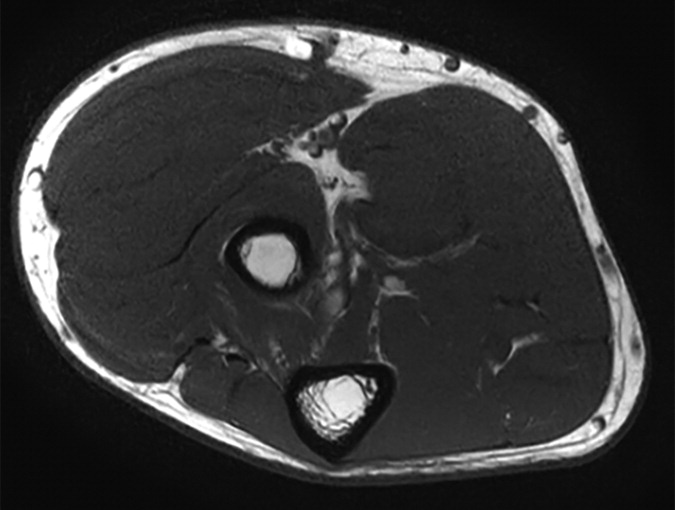

On the basis of the overall promising interrater agreement shown in this study, we believe that the newly proposed NS-RADS classification will perform as well in routine practice as it did in this initial validation study (Fig. 3).